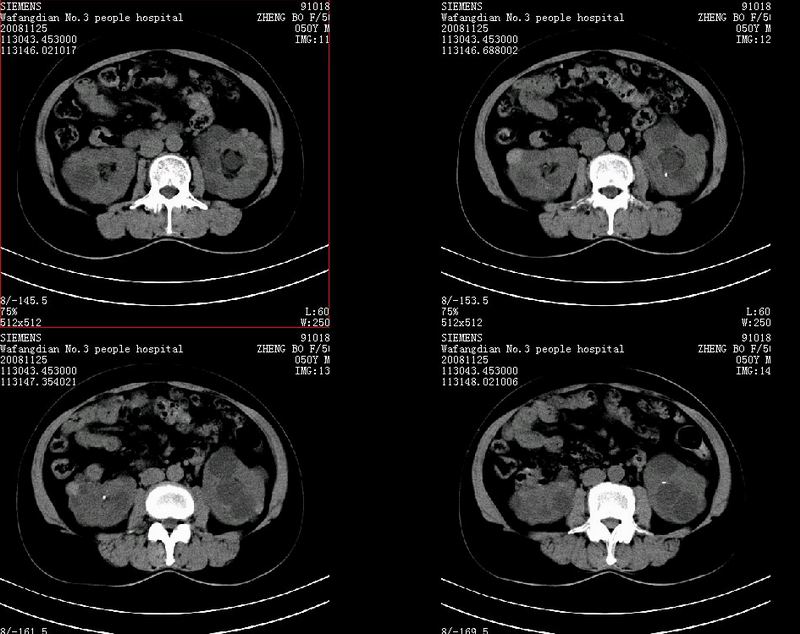

以下是引用guanaishengming在2008-12-4 12:28:00的发言:[br]多囊肾,密度高的为囊中内出血所致,双侧肾结石

以下是引用jiangjing在2008-12-4 14:09:00的发言:[br]多囊肾,密度高的为囊中内出血所致,双侧肾结石.建议增强检查及结合超声

以下是引用zjzjr在2008-12-4 13:14:00的发言:[br]也可能本身就是高密度肾囊肿.